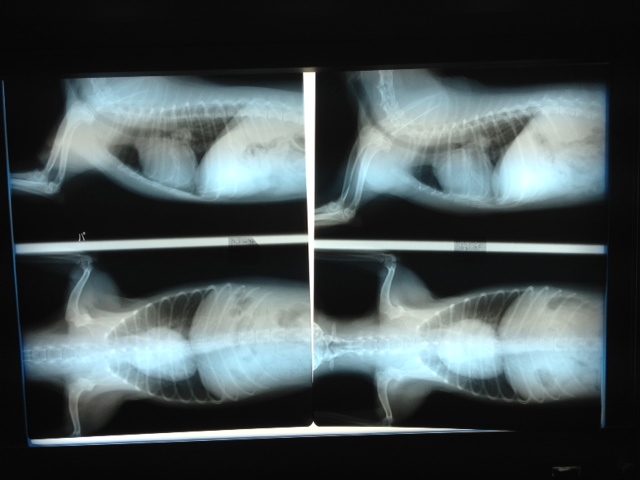

29日 ペットドック+レントゲン検査

昨年より一回り心臓肥大

左2011年6月、右2012年9月

薬が半錠増えました。